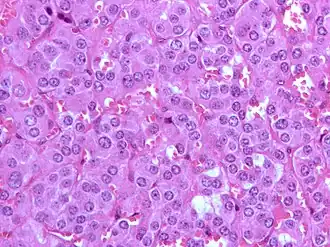

Un phéochromocytome est une affection tumorale parfois maligne. Cette tumeur se développe à partir des cellules chromaffines de la médullo-surrénale. Ne pas confondre avec le corticosurrénalome (en) qui, quant à lui, se développe à partir du cortex de la glande surrénale. Celui-ci se manifeste par une hypertension artérielle grave.

Sa première description remonte à 1886 par Félix Fränkel[3] chez une patiente décédée de ce qu'il pensait être un cancer des glandes surrénales. Le terme phéochromocytome apparaît en 1912[4] et correspond à une coloration particulière des tissus surrénaliens après fixation au chromate.

Il doit être évoqué devant les symptômes, l'imagerie retrouve une masse surrénalienne. Dans 10 % des cas on retrouve une masse extra-surrénalienne, on parle alors de paragangliome. Le diagnostic définitif est anatomo-pathologique.